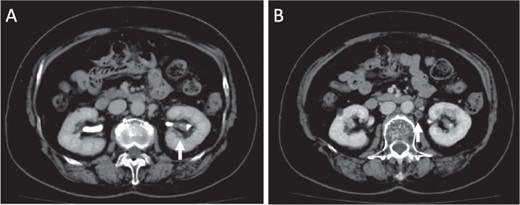

A 77-year-old Japanese woman visited a hospital following frequent and painful micturition for 2 weeks, with macrohematuria observed the day prior to consultation. She had hypertension and disk herniation of the lumbar spine. Although her urine showed microhematuria, atypical cells were not observed in her urine in the cytological screening performed at her initial visit to the hospital. Enhanced computed tomography (CT) scan revealed a tumor in the lower part of the left kidney and swelling of regional lymph nodes, suggesting lymph node metastasis of the tumor (Fig. 1). The tumor was mainly observed in the pelvis of the left kidney (Fig. 1A).

Images of enhanced CT scan. Enhanced CT revealed a 15-mm diameter tumor in the pelvis of the left kidney (A) and swelling of the regional lymph nodes, which showed a low-density area (B).